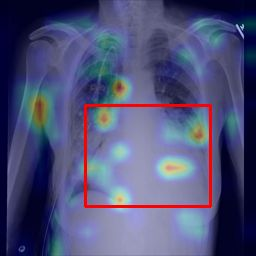

Deployments of artificial intelligence in medical diagnostics mandate not just accuracy and efficacy but also trust, emphasizing the need for explainability in machine decisions. The recent trend in automated medical image diagnostics leans towards the deployment of Transformer-based architectures, credited to their impressive capabilities. Since the self-attention feature of transformers contributes towards identifying crucial regions during the classification process, they enhance the trustability of the methods. However, the complex intricacies of these attention mechanisms may fall short of effectively pinpointing the regions of interest directly influencing AI decisions. Our research endeavors to innovate a unique attention block that underscores the correlation between 'regions' rather than 'pixels'. To address this challenge, we introduce an innovative system grounded in prototype learning, featuring an advanced self-attention mechanism that goes beyond conventional ad-hoc visual explanation techniques by offering comprehensible visual insights. A combined quantitative and qualitative methodological approach was used to demonstrate the effectiveness of the proposed method on the large-scale NIH chest X-ray dataset. Experimental results showed that our proposed method offers a promising direction for explainability, which can lead to the development of more trustable systems, which can facilitate easier and rapid adoption of such technology into routine clinics. The code is available at www.github.com/NUBagcilab/r2r_proto.